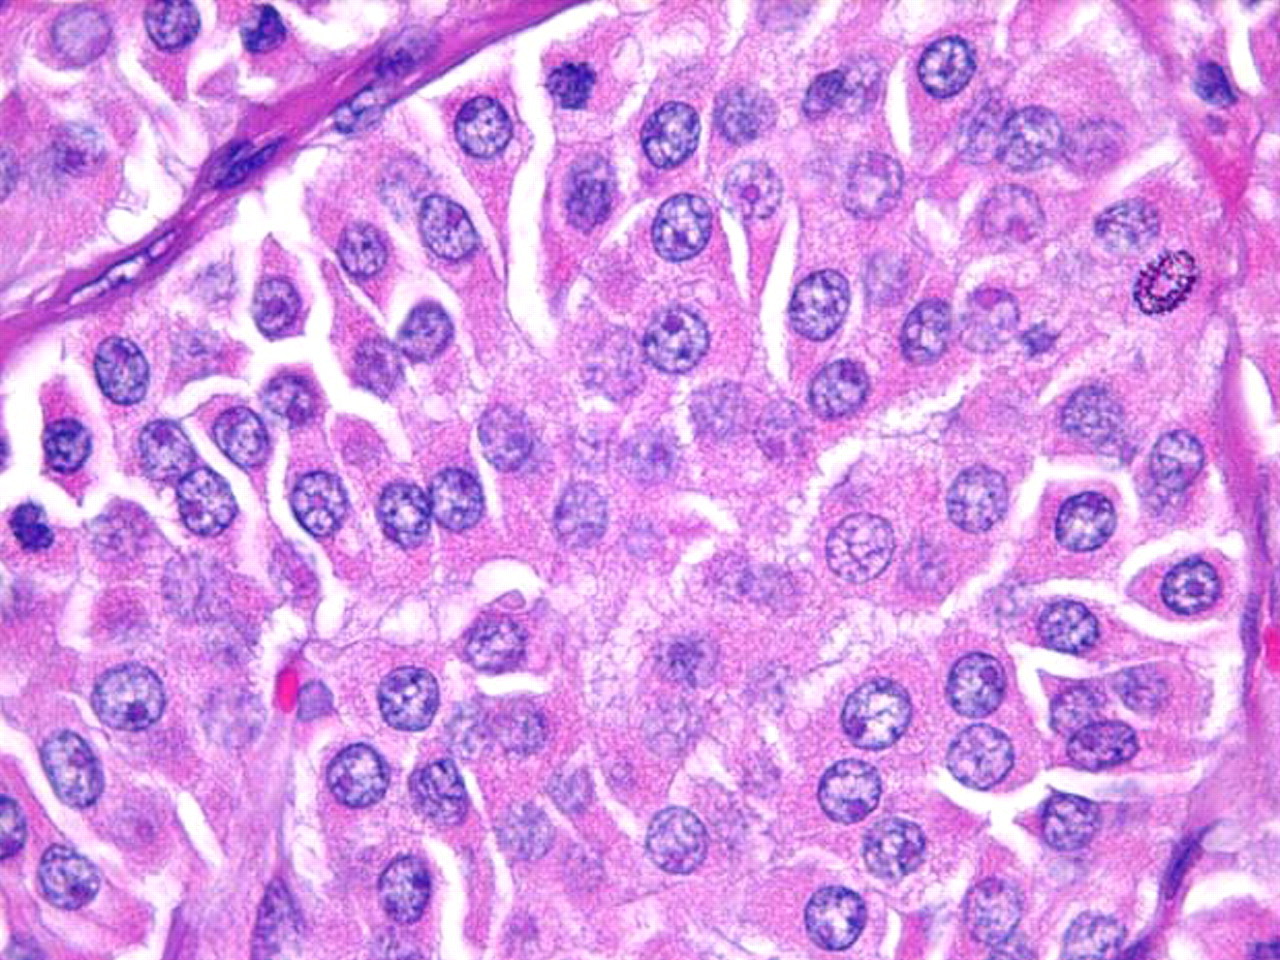

Oncocítico (anteriormente conocido como célula de Hürthle): representa entre el 3% y el 4% de los cánceres de tiroides.[2] Las células oncocíticas tienen un aspecto citológico clásico de células grandes con abundantes citoplasmas granulares eosinófilos y grandes núcleos hipercromáticos con nucléolos prominentes. Los carcinomas oncocíticos de tiroides son tumores malignos con invasión capsular y/o vascular, metástasis ganglionares o metástasis a distancia y se consideran más agresivos que los carcinomas foliculares de tiroides no oncocíticos.[2]

[Figure caption and citation for the preceding image starts]: Células oncocíticas (anteriormente conocidas como células de Hürthle) con abundante citoplasma granular eosinófilo y nucleolos de color "rosa cereza"Sandoval MAS et al. Case Reports 2011;2011:bcr1120103536; usado con autorización [Citation ends].